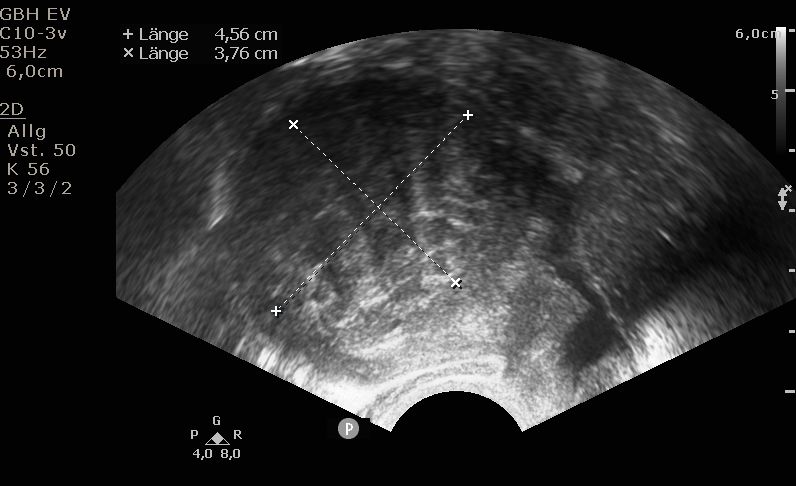

Die Diagnosestellung erfolgt in aller Regel mittels transvaginalem (durch die Scheide) Ultraschall. Nur in Ausnahmefällen ist eine MRT-Untersuchung notwendig.

Bei der Gebärmutterspiegelung wird die Gebärmutterhöhle mit Kochsalzlösung aufgedehnt. Eine Kamera mit integrierter Elektroschlinge wird in die Gebärmutter eingeführt. Die vorhandenen Myome können nun schrittweise unter Sicht abgetragen werden. Mittels modernsten Ultraschalluntersuchungen werden die Myome während der Operation noch einmal genau dargestellt. Bei sehr großen Befunden können zwei Operation zur kompletten Myomentfernung notwendig sein.